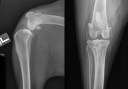

RadioQuiz 31 – Chien qui boite, la réponse

RadioQuiz 29 – Boiterie chronique

RadioQuiz 8

RadioQuiz 6 – la suite

RadioQuiz 6 – Ma p’tite chienne a mal à la patte

RadioQuiz 3: Docteur, mon chien boite…